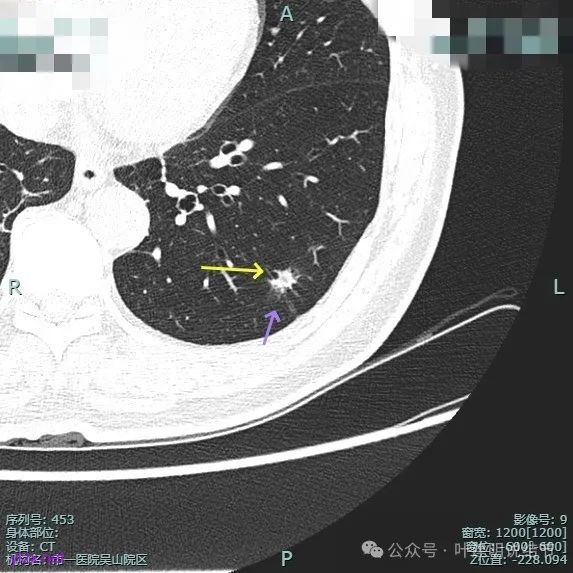

再看2024年10月时复查时我的意见:

对比至少没有进展,密度似略减低,考虑慢性炎伴纤维增生可能性大。

我们把三次薄层的放在一起看看: